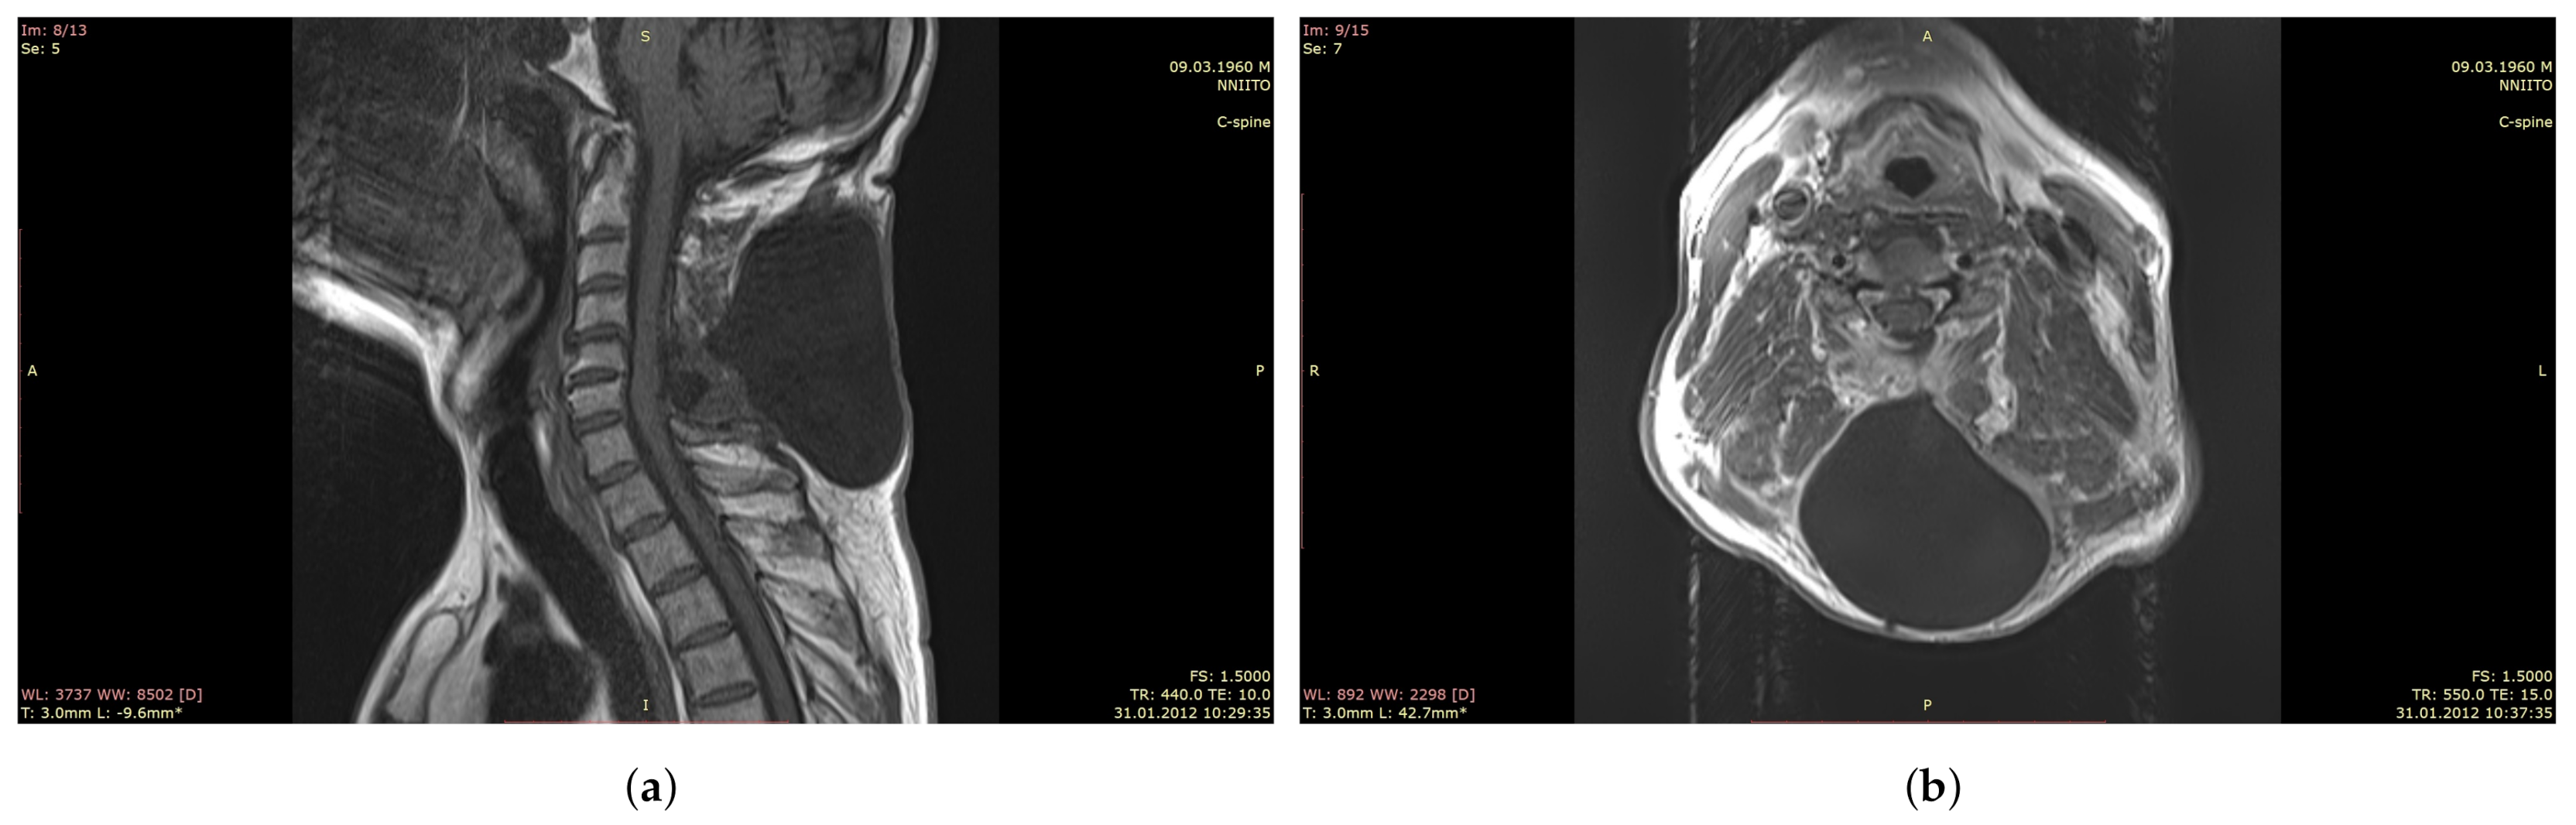

In addition, in violation of the dura mater integrity, fistulas and pseudomeningocele are formed (Figure 1). The latter is defined as a pathological extradural accumulation of cerebrospinal fluid in soft tissues communicating through a defect in the dura mater with the arachnoid space of the brain [4,5]. Figure 1 shows a cavity in the soft tissues of the cervical spine filled with cerebrospinal fluid (pseudomeningocele), which connects to the cerebrospinal fluid space of the spinal cord after removal of the extramedullary tumor and non-hermetic suturing of the dura mater. Plastic surgery on the dura mater is also necessary in cases of restoration of the lost part of the intrinsic dura mater associated with its invasion by a tumor, developed cerebral edema, elimination of cerebrospinal fluid fistulas, increase in the subdural space in Arnold–Chiari malformation, and myelomeningocele surgery [6].

Figure 1.

MRI of the cervical spine after removal of the spinal cord tumor and leaky suturing of the dura mater with the pseudomeningocele formation. (a): Sagittal plane, (b): Horizontal plane.